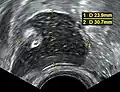

A small (4 cm) dermoid cyst of an ovary, discovered during a C-section

While all ovarian cysts can range in size from very small to quite large, dermoid cysts are not classified as functional cysts. Dermoid cysts originate from pluripotent germ cells (which are present at birth) that differentiate abnormally, developing characteristics of mature dermal cells. Complications exist, such as torsion (twisting), rupture, and infection, although their incidence is rare. Dermoid ovarian cysts which are larger present complications which might require removal by either laparoscopy or laparotomy (traditional surgery).[3][4] Rarely, a dermoid cyst can develop in the vagina.[5][6][7]